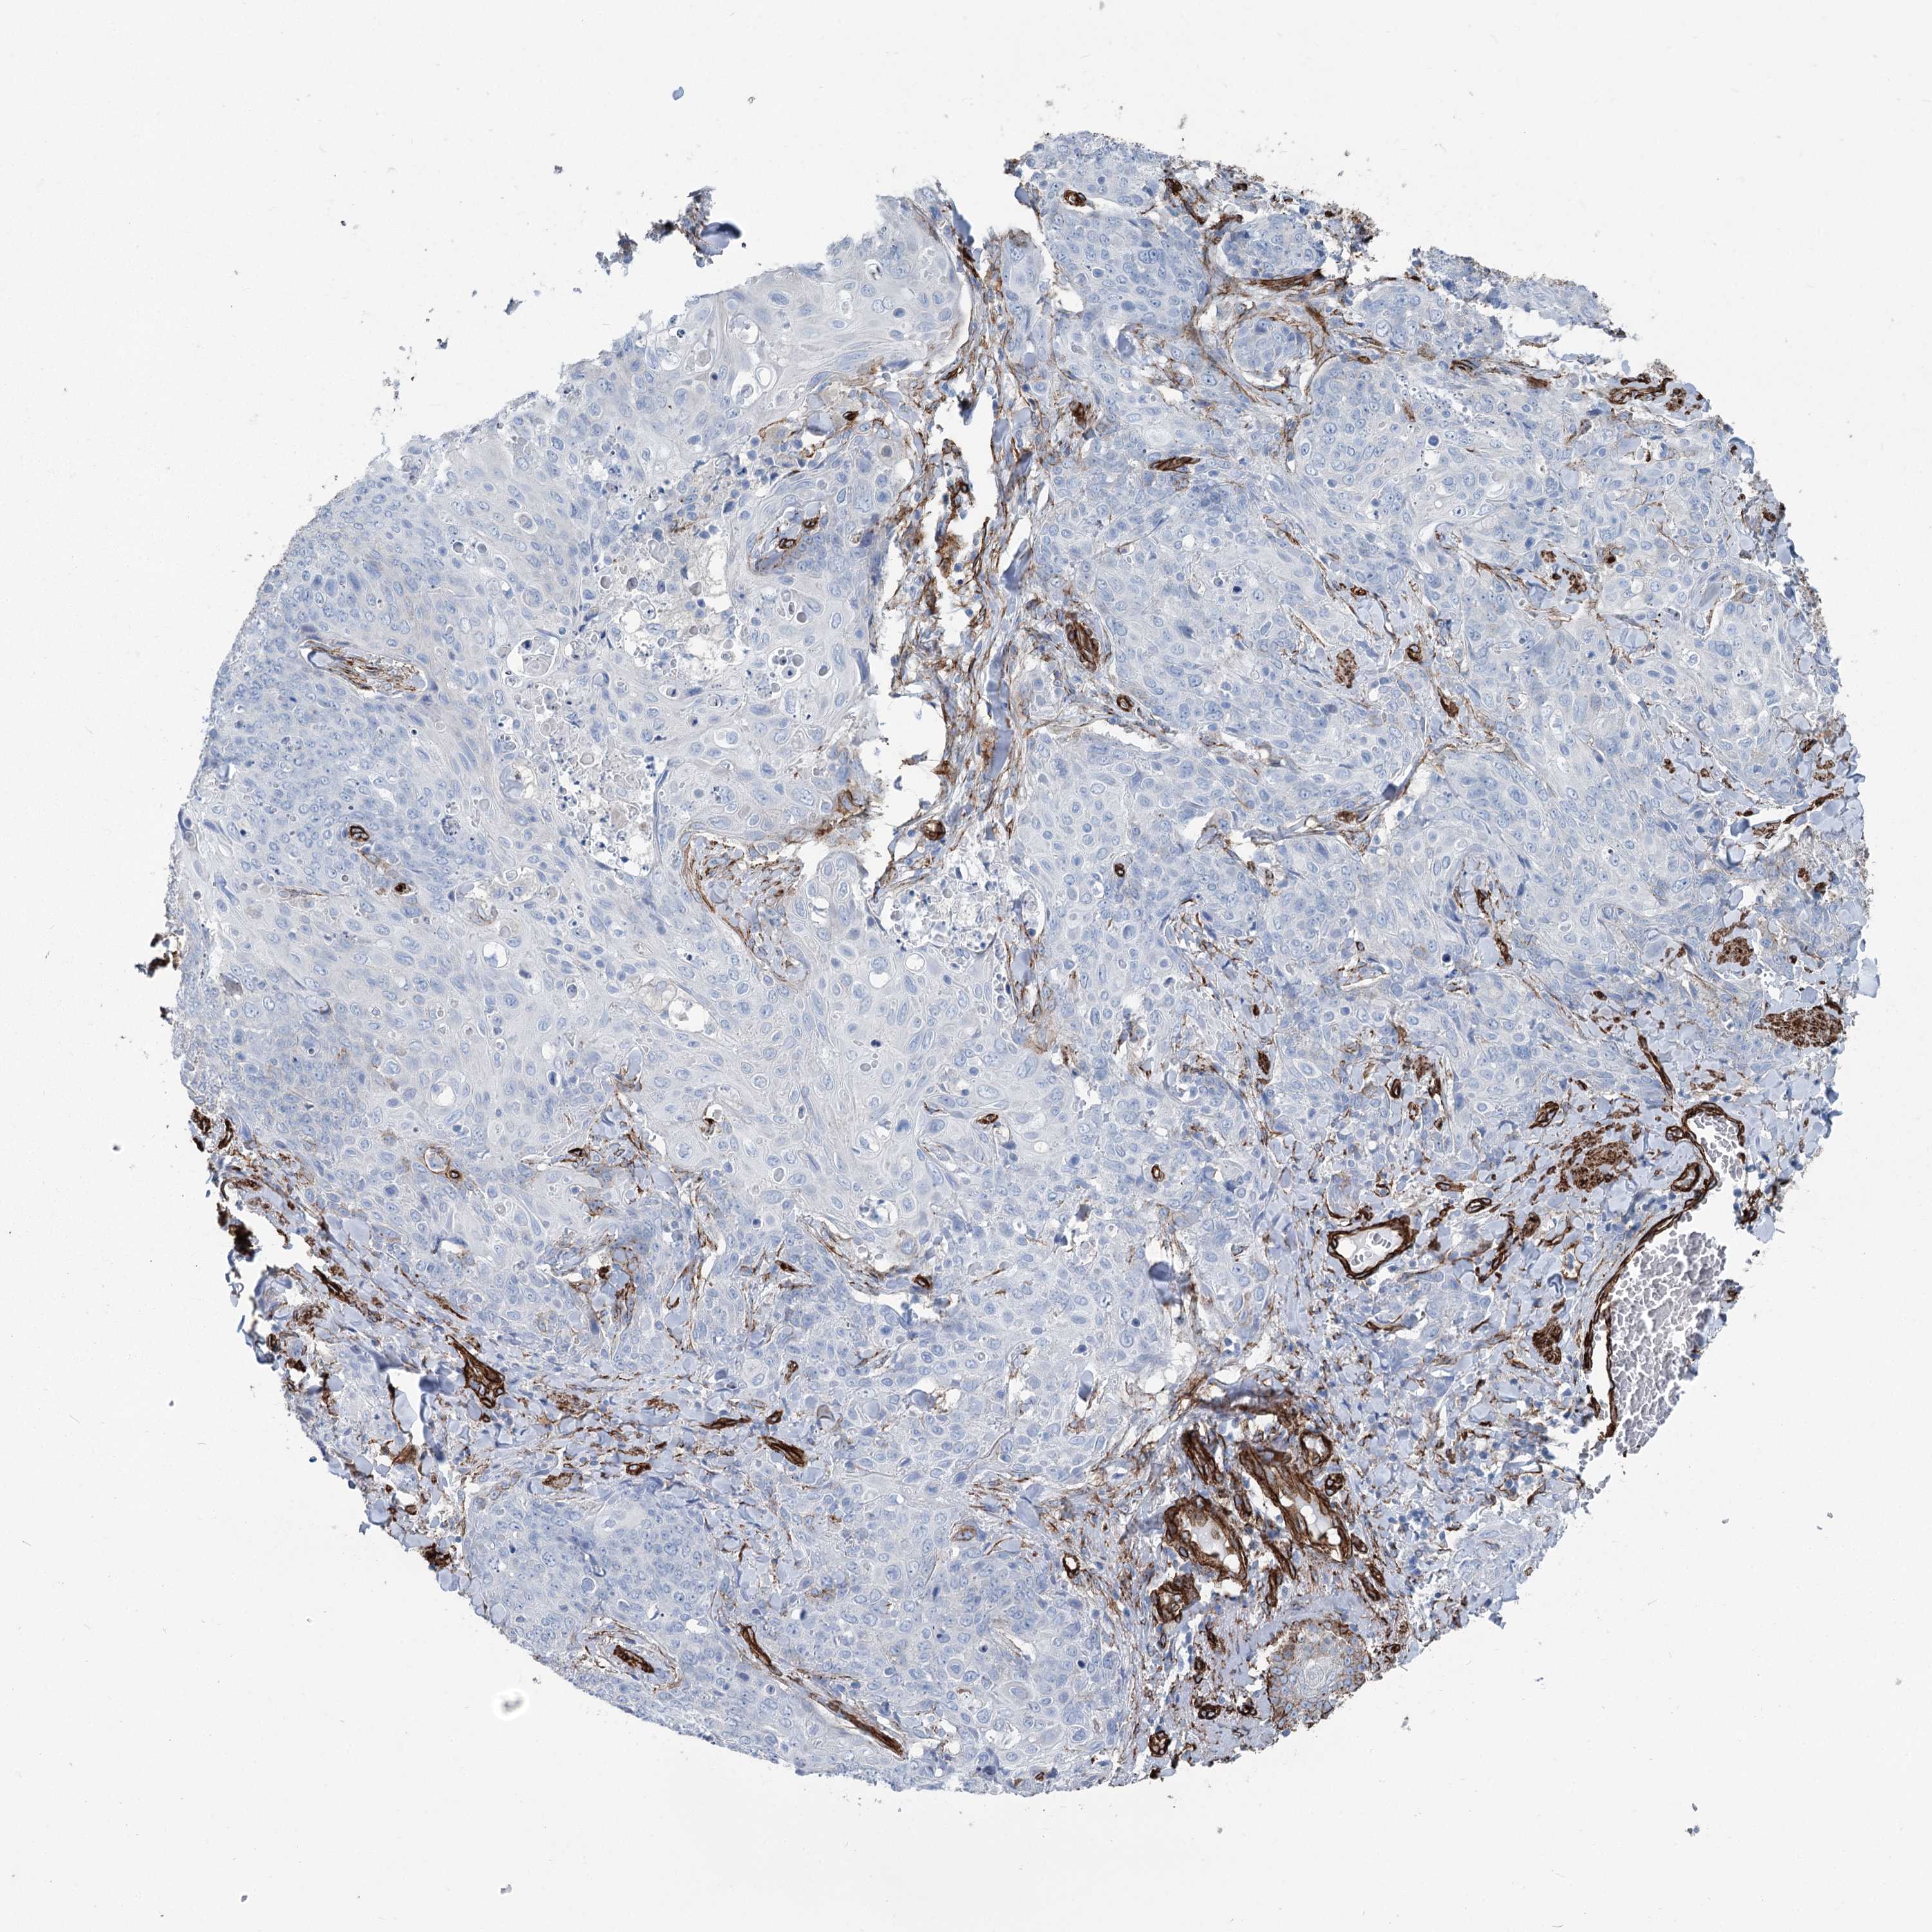

SKIN CANCER - Protein expressioni

A mouse-over function shows sample information and annotation data. Click on an image to view it in a full screen mode. Samples can be filtered based on level of antibody staining by selecting one or several of the following categories: high, medium, low and not detected. The assay and annotation is described here.

Antibody stainingi

Antibody staining in the annotated cell types in the current human tissue is reported as not detected, low, medium, or high, based on conventional immunohistochemistry profiling in selected tissues. This score is based on the combination of the staining intensity and fraction of stained cells.

Each image is clickable and will lead to virtual microscopy that enables deeper exploration of all samples and also displays staining intensity scores, fraction scores and subcellular localization as well as patient and tissue information for each sample.

Antibody HPA038143

Antibody HPA038144

Basal cell carcinoma

Squamous cell carcinoma, NOS

Squamous cell carcinoma, metastatic, NOS